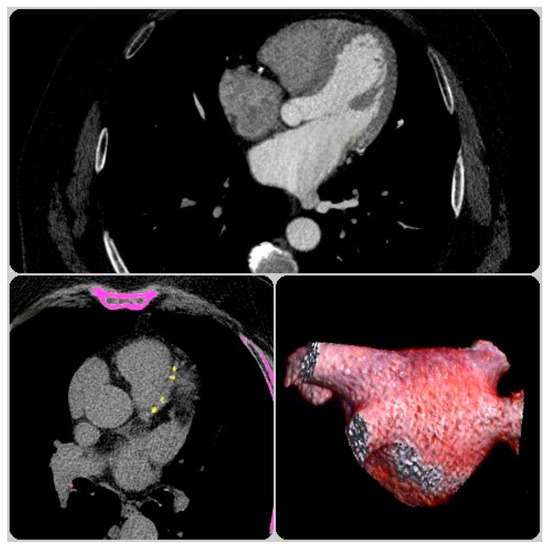

2.2.2. CCTA Analysis